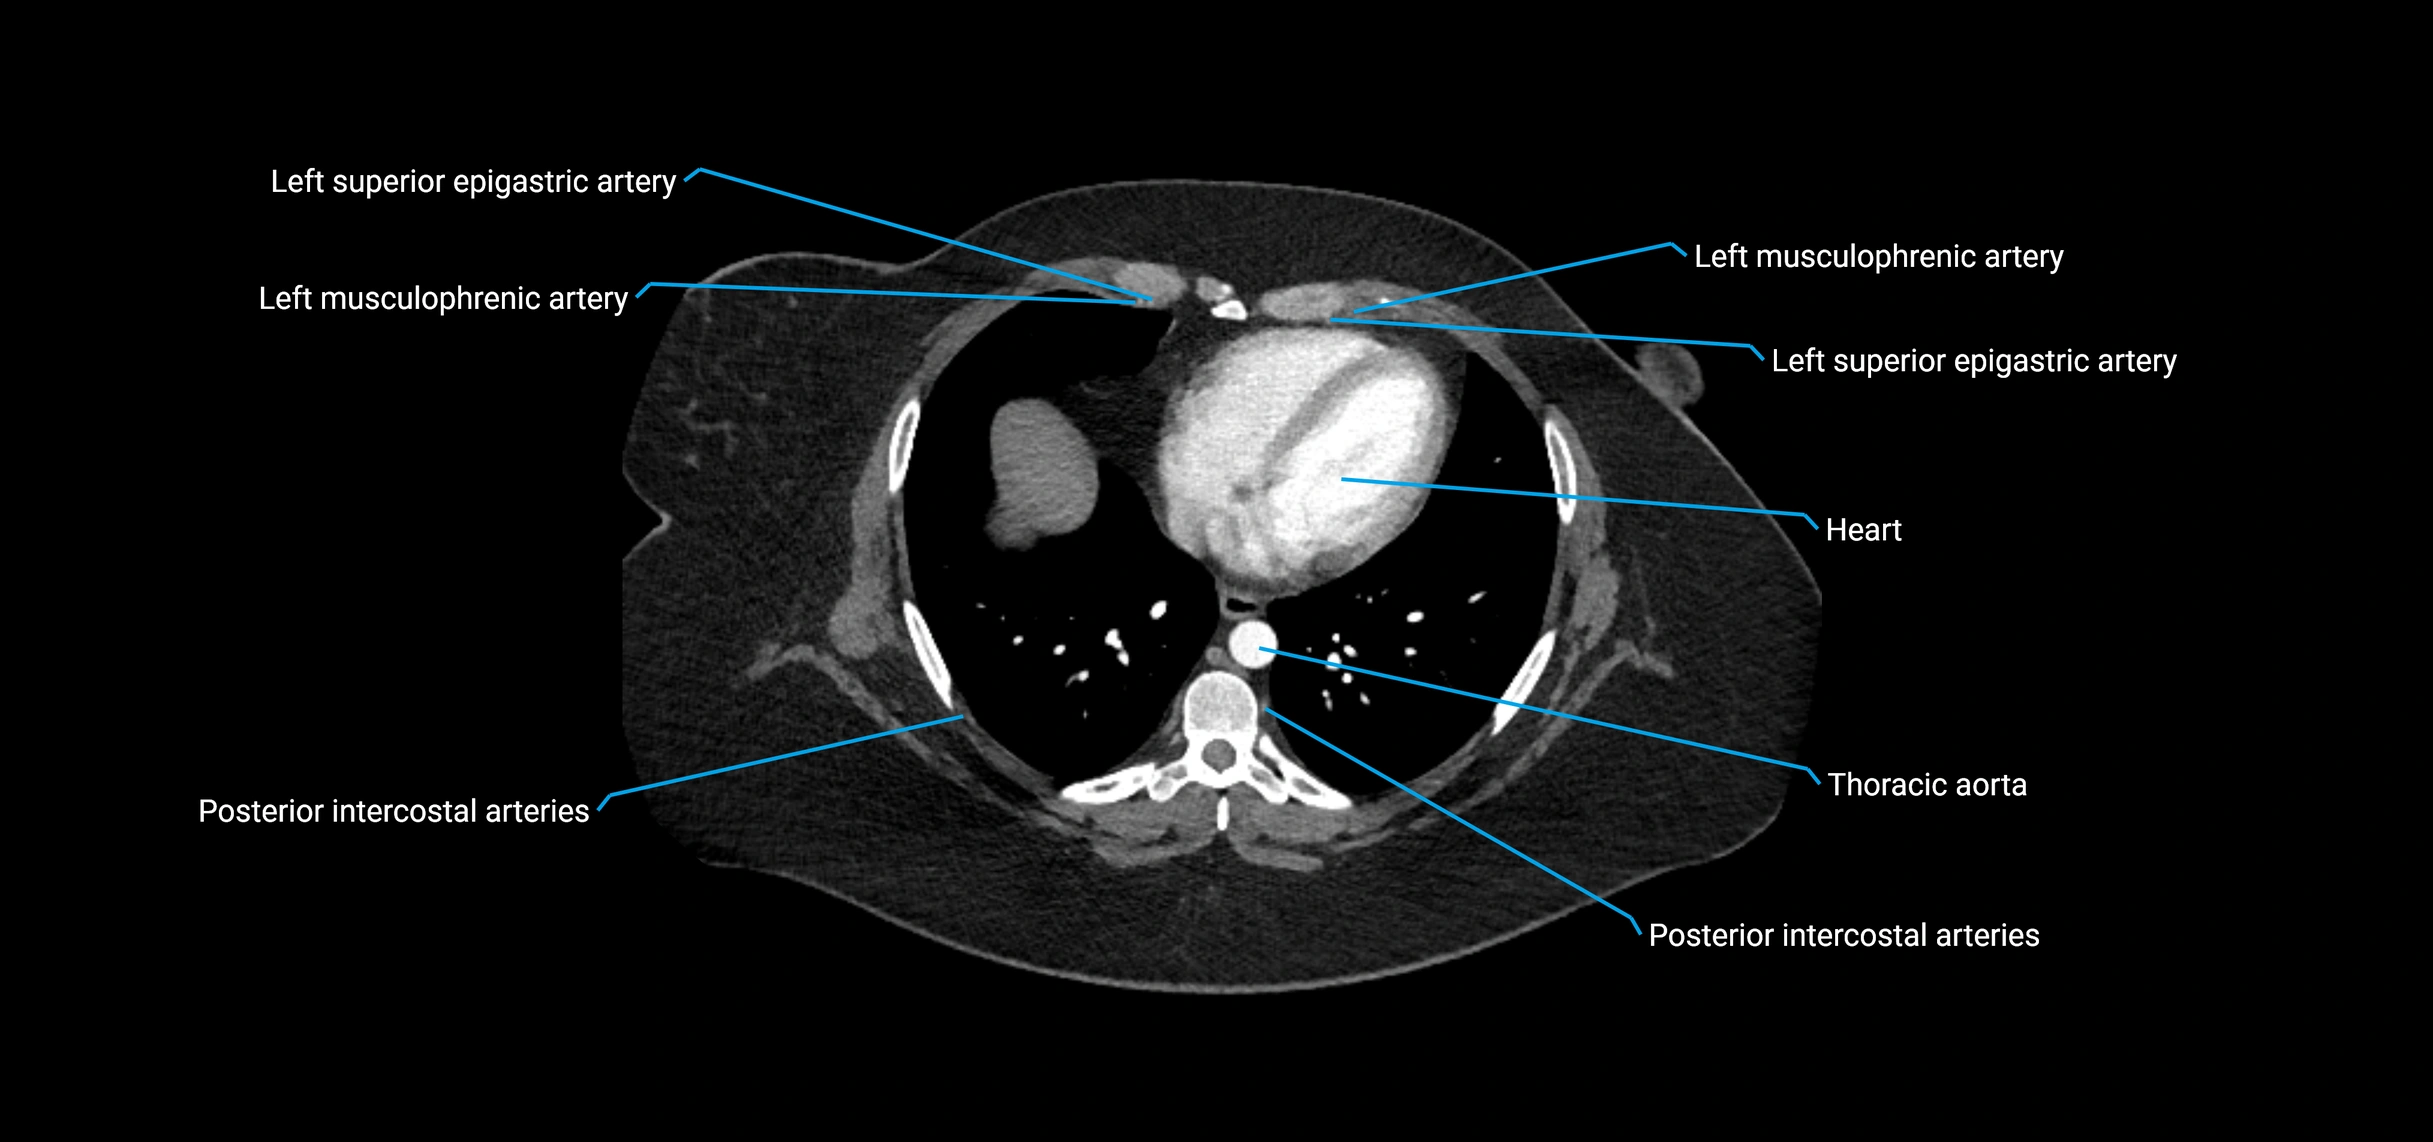

CT Appearance

Non-contrast CT:

• Appears as a tubular soft tissue structure anterior to vertebral bodies

• Calcified atherosclerotic plaques appear as hyperdense foci along the wall

• Useful for screening abdominal aortic aneurysm (AAA) size and mural calcification

Contrast-enhanced CT (CTA):

• Gold standard for abdominal aortic imaging

• Provides excellent detail of lumen, wall, aneurysm, thrombus, and branch vessels

• Multiplanar and 3D reconstructions help in aneurysm measurement, stent graft planning, and dissection evaluation